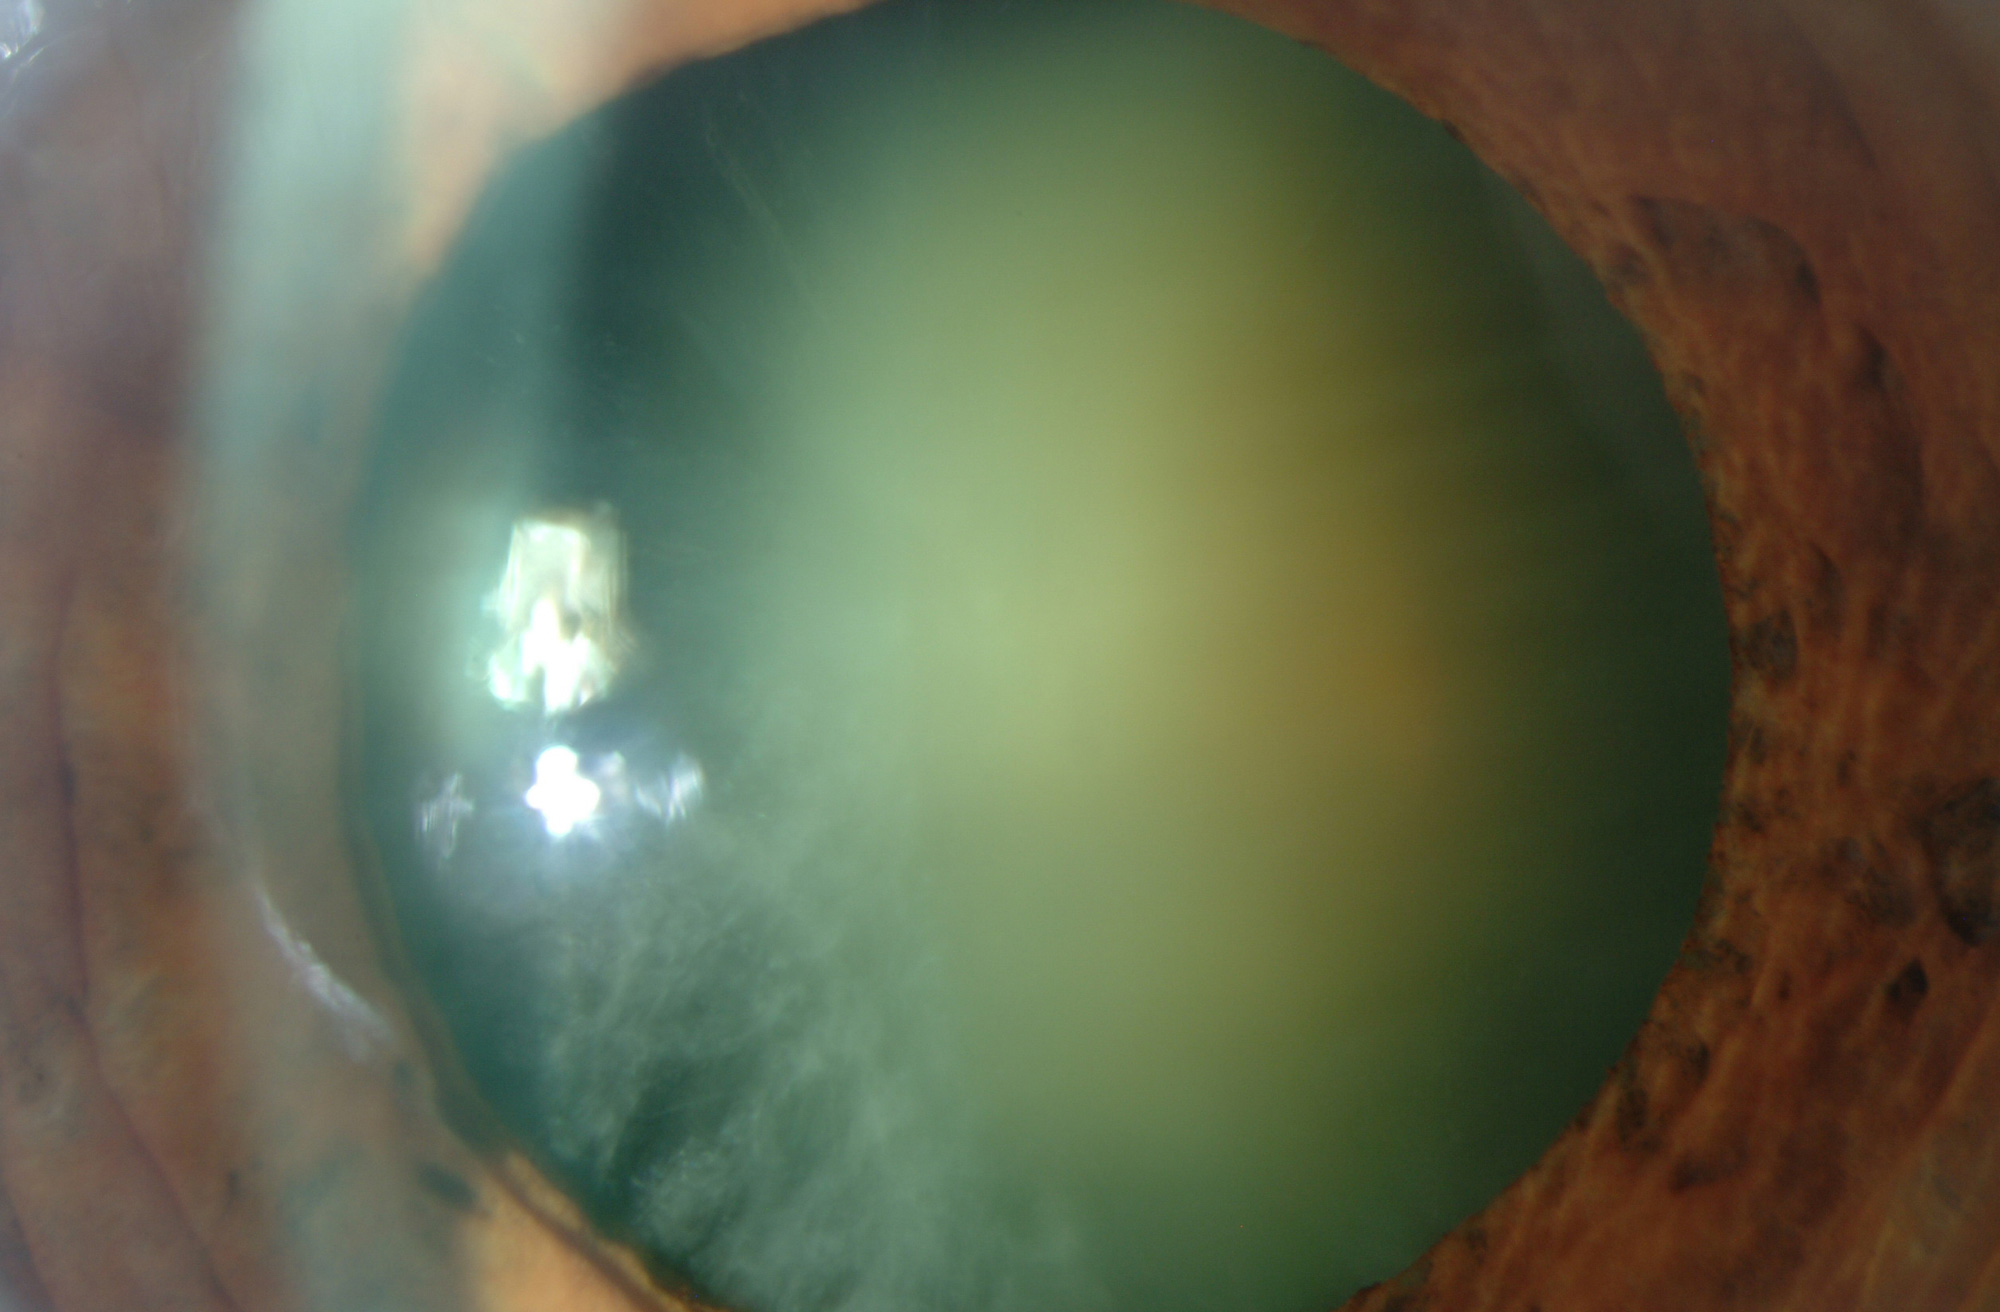

La catarata es la opacidad parcial o total del cristalino que se manifiesta por una pérdida de visión progresiva. En la mayoría de casos, la catarata suele aparecer con el envejecimiento a partir de los 60 años.